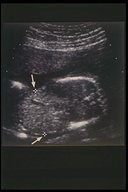

The abdominal wall defect can be diagnosed prenatally by ultrasonography